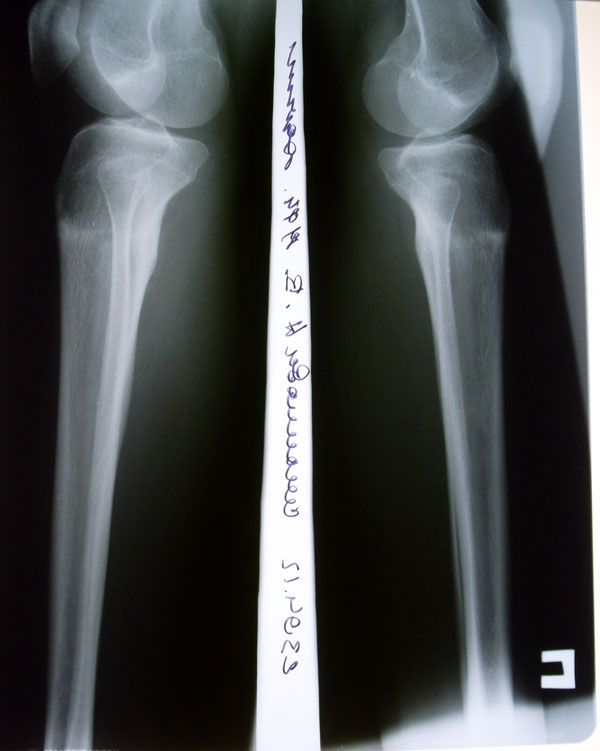

Рентгеновские снимки от 23.04.2012г. Аппаратная жизнь в аппаратах Илизарова-Онипко 57 дней.

Вложения

SAM_2491.JPG

SAM_2488.JPG